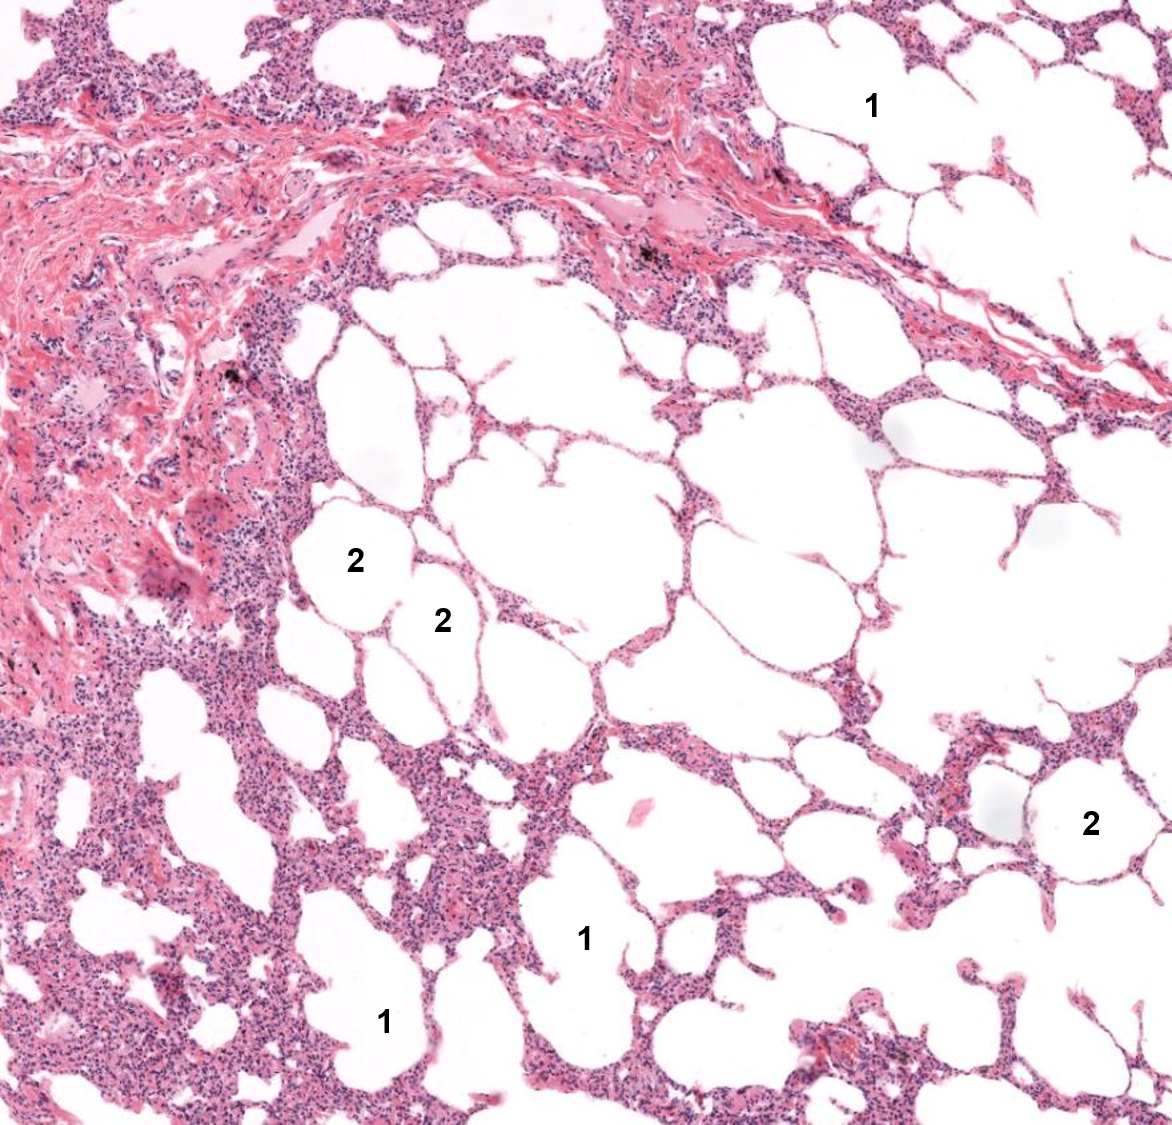

Pulmão

1: Alvéolo

2: Ducto alveolar

1: Saco alveolar

2: Alvéolo